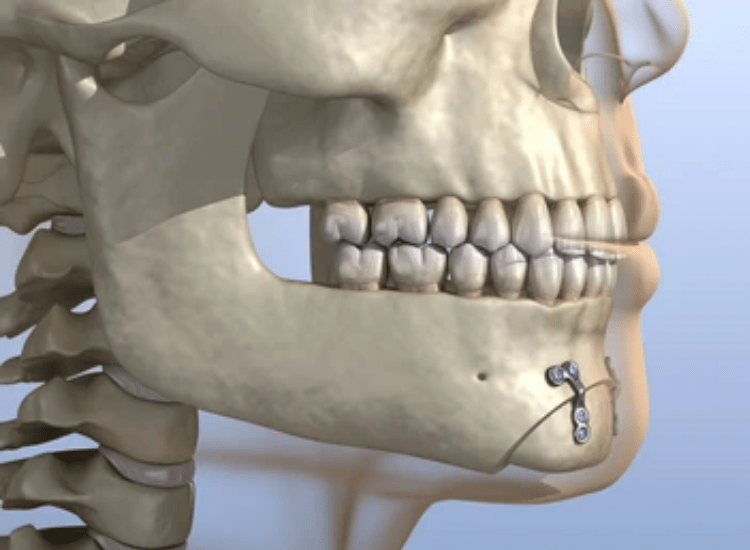

Genioplasty is a form of cosmetic surgery that involves repositioning or reshaping the chin to improve facial harmony. Oral-maxillofacial surgeons with specific training and experience in treating the head, face, mouth, and jaw typically perform Genioplasty procedures.